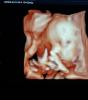

28.11.2024

так ручками закрыл личико 🥹

umm Zakariya🪴☁️·Мама дочки-младенца

я думала это и есть 4d

оказывается это 3d🌝